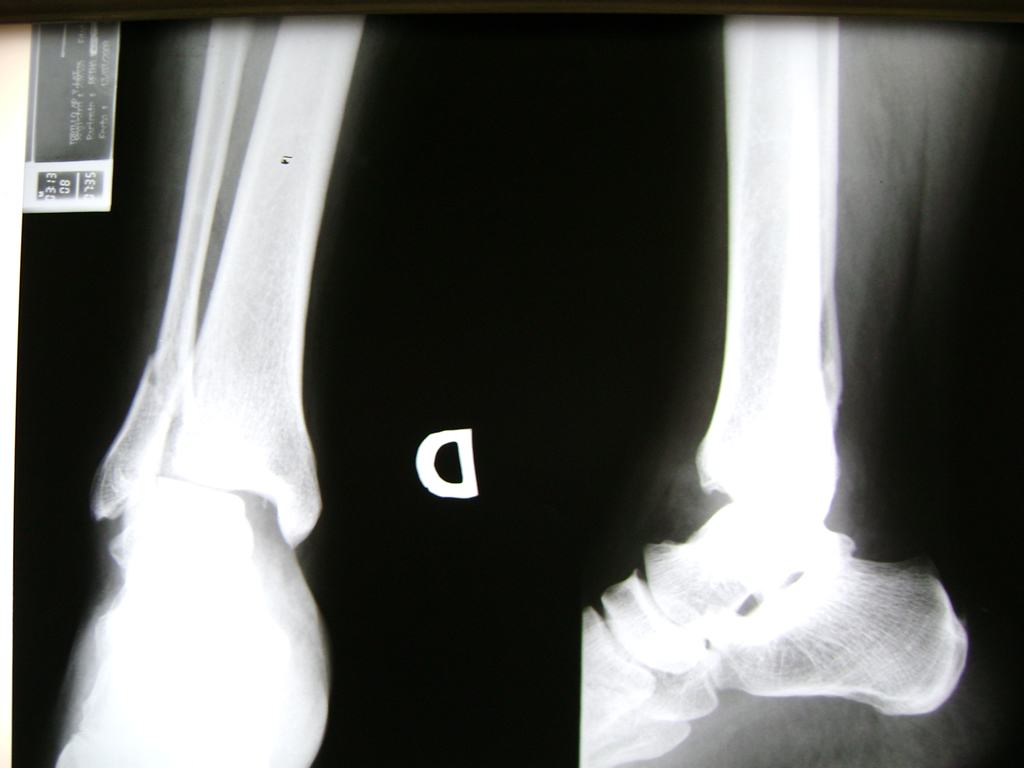

Una fractura de tobillo es la rotura de uno o más de los huesos del tobillo. Estas fracturas pueden ser:

- Los extremos de los huesos están desalineados entre sí (desplazados).

- La fractura se extiende hasta la articulación del tobillo (fractura intra-articular).

Cuando se necesita cirugía, es probable que esta implique el uso de clavijas de metal, tornillos o placas para sostener los huesos en su lugar mientras la fractura se consolida. Los elementos de soporte pueden ser temporales o permanentes.